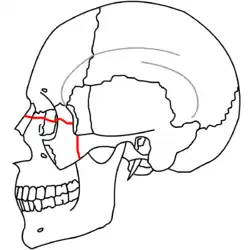

|

| Le Fort III fractures | |

At the beginning of the 20th century, René Le Fort mapped typical locations for facial fractures; these are now known as Le Fort I, II, and III fractures (right).[7] Le Fort I fractures, also called Guérin or horizontal maxillary fractures,[14] involve the maxilla, separating it from the palate.[15] Le Fort II fractures, also called pyramidal fractures of the maxilla,[16] cross the nasal bones and the orbital rim.[15] Le Fort III fractures, also called craniofacial disjunction and transverse facial fractures,[17] cross the front of the maxilla and involve the lacrimal bone, the lamina papyracea, and the orbital floor, and often involve the ethmoid bone,[15] are the most serious.[18] Le Fort fractures, which account for 10–20% of facial fractures, are often associated with other serious injuries.[15] Le Fort made his classifications based on work with cadaver skulls, and the classification system has been criticized as imprecise and simplistic since most midface fractures involve a combination of Le Fort fractures.[15] Although most facial fractures do not follow the patterns described by Le Fort precisely, the system is still used to categorize injuries.[5]